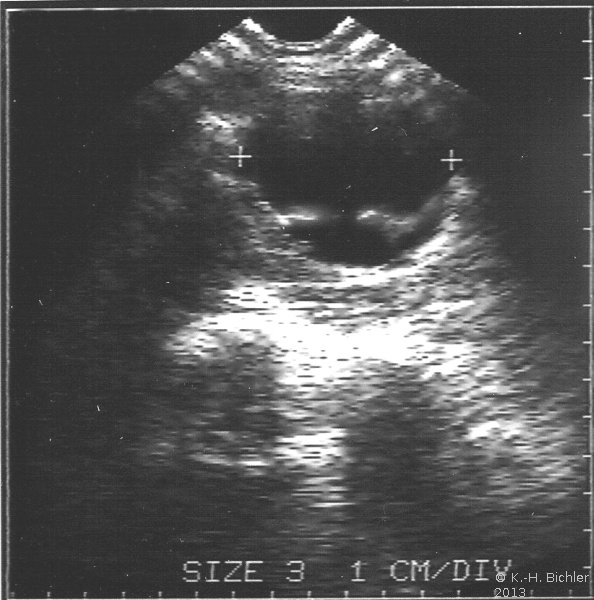

Am Beginn der Diagnostik steht die Sonographie (Abbildung 6). Neben dem Tumornachweis und der Zugehörigkeit zur Niere ist der Nachweis einer eventuellen Tumorinvasion in die Nierenvene (u.U. im Rahmen einer farbkodierten Dopplersonographie) bzw. in die Vena Cava inferior von Interesse. Immerhin bricht der Tumor in 11% in die Nierenvene und zu 6% in die Vena Cava ein, selten bis in das rechte Atrium (s. auch Abbildung 1c)

Der Wert der FKDS (farbkodierte Dopplersonographie= Angiodynographie = Farbdoppler) bzw. der kontrastverstärkten Sonographie ist zur Zeit noch nicht hinreichend belegt. Eine Verbesserung der Ergebnisse, auch hinsichtlich der Beurteilung der Nierenvene (z.B. Tumoreinbruch) ist zu erwarten